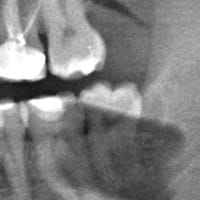

Es normal que me hagan una reconstrucción de una muela y no me quiten una caries interdental de la de atrás?

Fui al dentista para hacerme una reconstrucción de una muela que tenia rota. Al día siguiente volví porque me molestaba un poco puesto que me la había dejado un poco alta para mi sorpresa cuando vuelvo a casa me encuentro que en la muela de atrás...